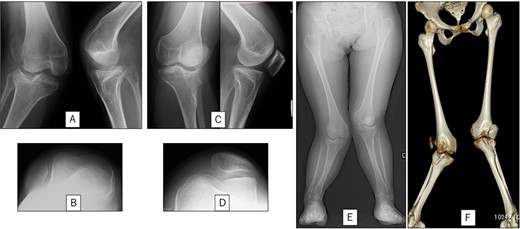

A 23-year-old woman presented with bilateral knee pain and gait abnormalities owing to marked lower extremity deformity. She was diagnosed with EVC as a child but had never been followed up by orthopedics because she was not in pain. On physical examination, marked valgus instability was observed in both knees, and the motion of both knees ranged from 10° to 135°. Radiographic examinations of both knees, including computed tomography, showed valgus deformity, lateral and anterior depression of the proximal lateral tibial plateau, and external rotation deformity of the lower leg. Patellar dislocation was observed in the right knee (Fig. 1). The radiological angles are presented in Table 1. The right knee underwent surgery first, followed by the left 10 months later. Lateral and medial skin incisions were made. Extensive lateral retinacular release, fractional lengthening of the distal lateral hamstring, and Z-lengthening of the iliotibial band were then performed. At this stage, peroneal nerve strain was identified, and decompression of the peroneal nerve was performed. Osteotomy was subsequently performed on the tibia. Closed-wedge varus and derotational osteotomy of the proximal tibia and open-wedge varus osteotomy of the distal femoral varus were performed. In addition, vastus medialis advancement was performed on the right knee, and patellar realignment was achieved in extension (Fig. 2). However, the knee showed a subluxation tendency owing to flexion of >30°; therefore, the postoperative rehabilitation plan progressed more slowly than that of the left knee. Range of motion training began on the left knee immediately after surgery without any restrictions, but on the right knee only after 3 weeks of postoperative immobilization in the extended position. However, ambulation exercise was performed on both knees with no loading for 3 weeks, then partial loading was initiated, and full loading was permitted at 8 weeks postoperatively. Early postoperative standing radiography showed residual mild valgus deformity of the lower limbs (Fig. 2, Table 2). In addition, the right knee showed patellar re-dislocation 2 months postoperatively, and the patellar deformity gradually progressed owing to the femoral implant; therefore, the patient underwent implant removal, tibial tubercle transfer, and medial patellofemoral ligament reconstruction 1.5 years after the initial surgery (Fig. 3). Six months later, she fell while walking and developed a fracture at the osteotomy of the right femur; open reduction and internal fixation were performed (Fig. 4). The remaining years passed uneventfully, and 10 years after the initial surgery, the patient still had mild valgus deformity of the lower limbs, but had no recurrence other than that experienced immediately after surgery, no complaints of knee pain, and a stable gait (Fig. 5, Table 2).

Postoperative radiography: (A) immediate postoperative radiograph of the right knee, (B) immediate postoperative radiograph of the left knee, (C) the entire lower limbs at 2 months after left knee surgery. Mild valgus deformity of the lower limbs persisted.